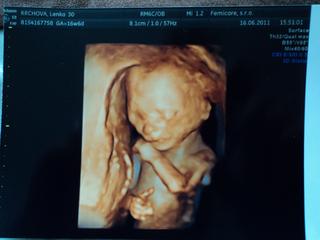

čaute baby, včera som preto až tak neskoro pisala, lebo rovno z utz som išla pomocť kamoške, ktora preraba detsku izbu.dneska som bola na tom druhom vyšetrni, všetko je ok, už bolo vidno aj žaludok, včera bolo len zle otočene, tak sa tešim,maly je zdravučky!klop klop klop 🙂

ahojte baby, tak my sme sa po 3. tyzdnoch vratili zo Slovenska. Bola som prvy krat na ultrazvuku v mojom 18 tt a vsetko dopadlo super, babo je zdrave, rastie a je to dievcatko, takze sa velmi tesime. Stihli sme aj nakupy ... kedze v Nitre uz boli vypredaje ... tak som pokupila zimne vecicky ktore najviac vyuzijeme.